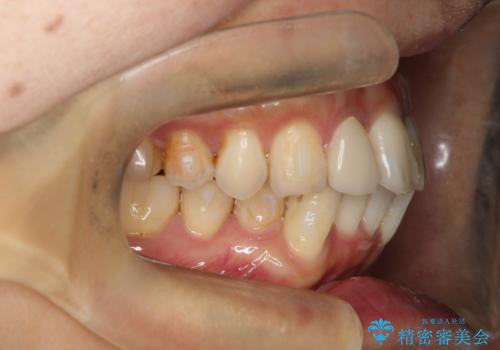

- 全体的なガタガタと前歯をきれいにしたいとのことで来院されました。

下の歯は重度のガタガタがあり、上の前歯は何本かが神経の治療がしてある状態でした。

インビザラインにて歯並びを整え、上顎の前歯にセラミックを装着する計画としました。